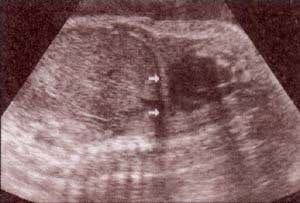

fig 28. – (a). pulmones corte coronal. 32 semanas. |

fig. 28. – (b). corte transversal. 32 semanas. |